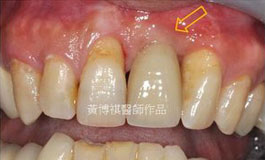

前牙植牙補骨手術範例: |

術後完成照。 |